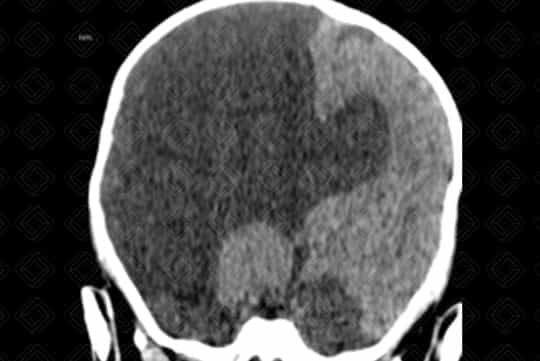

Descrição da lesão: Tomografia computadorizada do crânio com reformatações nos planos coronal e axial. Fenda preenchida por densidade liquórica na região parietal direita, caracterizando esquizencefalia de "lábios abertos" (primeira imagem).

Esquizencefalia : Trata-se de fenda transcortical delimitada por substância cinzenta. Elas podem ser de lábio aberto (grande defeito) ou lábio fechado (pequeno defeito). Até metade das esquizencefalias são bilaterais. Quando bilaterais, até cerca de 60% das esquizencefalias são de "lábios abertos" de ambos os lados.

• Tomografia computadorizada do crânio: N a tomografia de crânio é de fácil visualização o defeito e sua comunicação com o sistema ventricular. Vale lembrar que a ausência de septo pelúcido está presente em quase todos os casos;